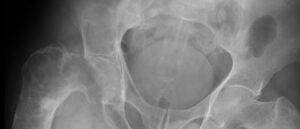

Хондромиксоидные фибромы

Опухолевое новообразование может поражать хрящевую ткань в разных отделах трубчатых костей скелета человека. Хондромиксоидная фиброма — так в медицине называется такая хрящевая опухоль. Фиброму, состоящую из хрящевой ткани, можно встретить нечасто, но она способна поражать людей любого возраста и пола. В большинстве случаев начальная стадия ее развития протекает бессимптомно. С ростом появляется угроза дальнейшего злокачественного …